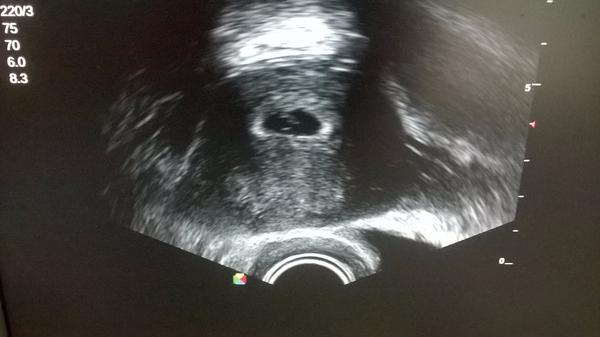

Ahoj holky. Tak sem to dneska nevydržela a jela k doktorovi. Jelikož mě docela vyděsil ten malý počet týdnů na digitálu, tak sem se bála, že to bude ZT. Včera mě navíc začalo bolet břicho jako na MS a na záchodě po utření trošičku světle hnědého hlenu, takže sem se rozhodla, že budu radši za hysterku a zajdu k dr.Nervičky pracovaly jak sviňa. A výsledek? Je tam prý malinký hematom ale nešpiním, tak je to ok 🙂. Ale co je hlavní - oproti minule co tam šla vidět pidi tečka sme krásně porostly a byl už i náznak srdíčka.. Vím, že to není ještě velká výhra ale sem ráda

@lucky22 gratulace holky 🙂, já sem dneska taky byla a byl už náznak srdíčka 🙂 jsme ještě malincí ale vypadá to dobře 🙂